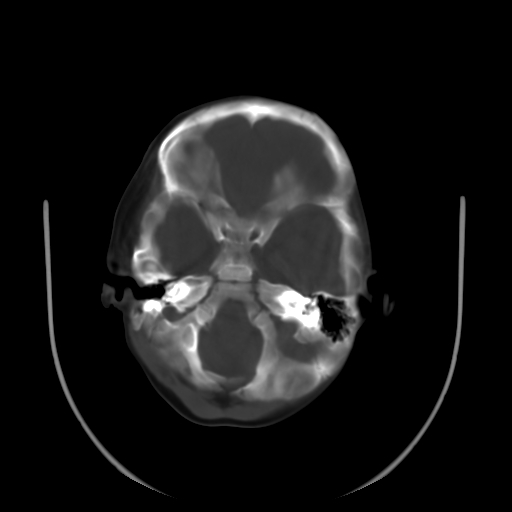

以下是引用深泽交通医院在2009-10-16 8:25:00的发言:[br]右眼环出血伴异物

以下是引用卜一在2009-10-16 15:01:00的发言:[br]右眼球挫裂伤伴异物!

以下是引用拾荒者在2009-10-17 18:38:00的发言:[br]鼻面部皮下积气,右侧睑缘及眼球壁高密度异物影,左侧眼球壁晶状体内侧缘处是圆形低密度影。低密度异物?应提请眼科医生注意。